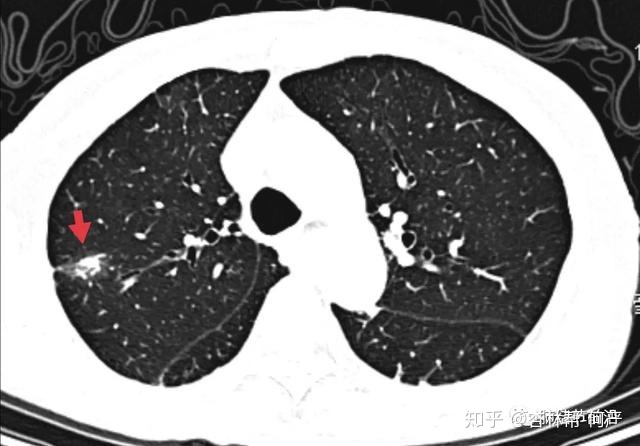

结节1:7mm实性结节,边界光滑,CT图像大概率为良性结节。

结节1:CT值为197,诊断为纤维灶结节。

这个右上肺结节CT值也很高>200,但是其周边出现了磨玻璃影,为贴壁样生长的肺癌。术后病理为:微浸润腺癌。因此,纤维灶附近出现边界清楚的磨玻璃影,也是需要警惕的。